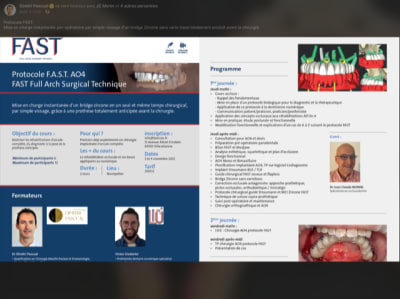

Tu as ouvert un post clinique : quel type de guide et pourquoi faire .

Toutes tes interventions sont en fait pour arriver à la conclusion que le mieux , c’est un guide métallique, stérilisable, à appuis osseux , avec une mise en charge immédiate en fin de chir.

Je te montre donc un protocole qui utilise un guide métal , à appuis osseux, avec mise en charge instantanée d’un bridge zircone définitif.

D’ailleurs, tu m’avais demandé le coût . Je n’ai même pas posé la question . C’est sur deux jours. Cela t’intéresse ?